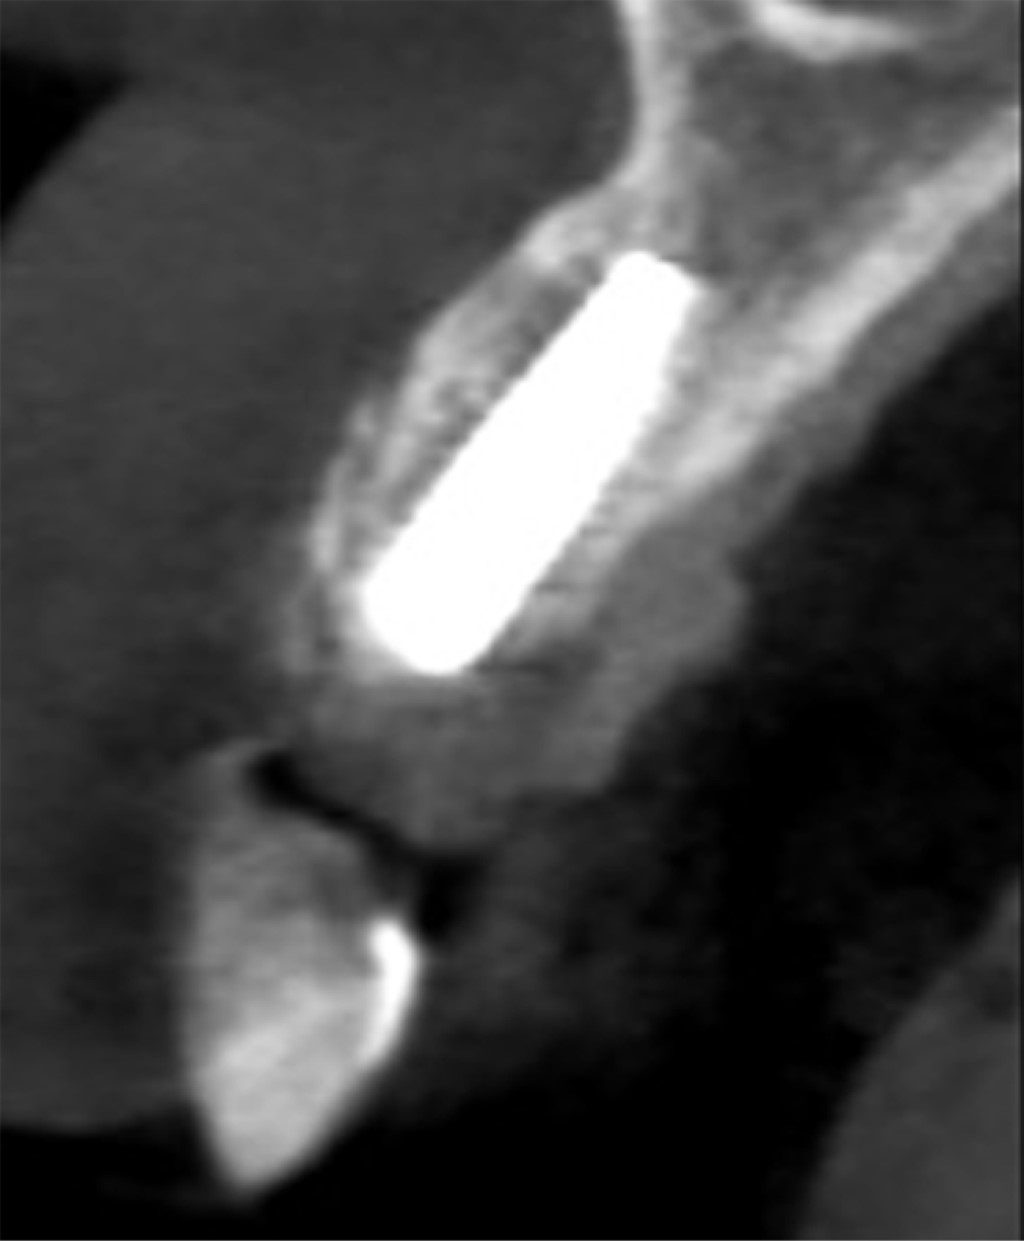

COLOCACIóN DEL IMPLANTE DENTAL

En la segunda fase quirúrgica, posterior a cinco meses, se solicitó a los pacientes tomografía Cone Beam para control postoperatorio, donde fue evidente una ganancia ósea en sentido horizontal de 2 a 5 mm aproximadamente en comparación con la deficiencia inicial (Figura 4A-D), los pacientes fueron llevados nuevamente a mesa operatoria bajo anestesia local, previa antisepsia del campo operatorio, se infiltró lidocaína al 2% más epinefrina 1:100,000 para bloqueo del nervio alveolar anterior, se abordó la zona con una incisión supracrestal con descargas laterales sin incluir papilas, se hizo levantamiento de colgajo mucoperióstico a espesor total, exponiendo la zona receptora y evidenciando clínicamente la completa integración del injerto a la zona receptora (Figura 5A), se procedió a retirar el material de osteosíntesis y a colocar el implante dental en la zona (Figura 5B y C), de forma satisfactoria y sin complicaciones, posteriormente, se realizó el control postquirúrgico del implante dental y se observó el mismo en posición y cubierto de hueso en su periferia (Figura 6).